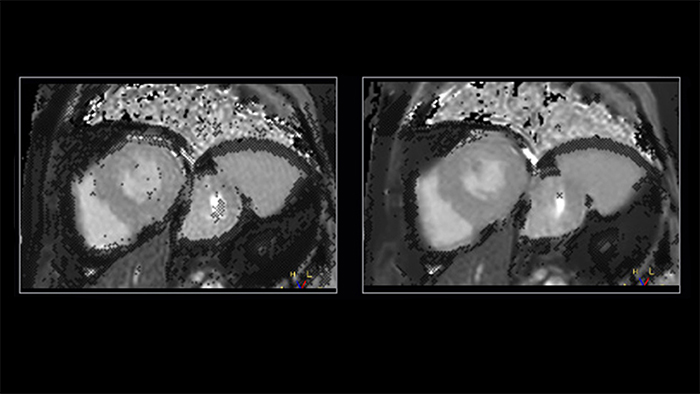

Shorter data readouts [2] enabled by Compressed SENSE provide benefit for black bloods and T1 mapping as well with sharper images acquired. For T1 mapping this results in fewer unconfident pixels on the resulting T1 map (see Fig. 3).

Figure 3. T1 mapping: shorter readouts using C-SENSE x3 leads to fewer unconfident pixels. Left to right: SENSE x2, C-SENSE x3